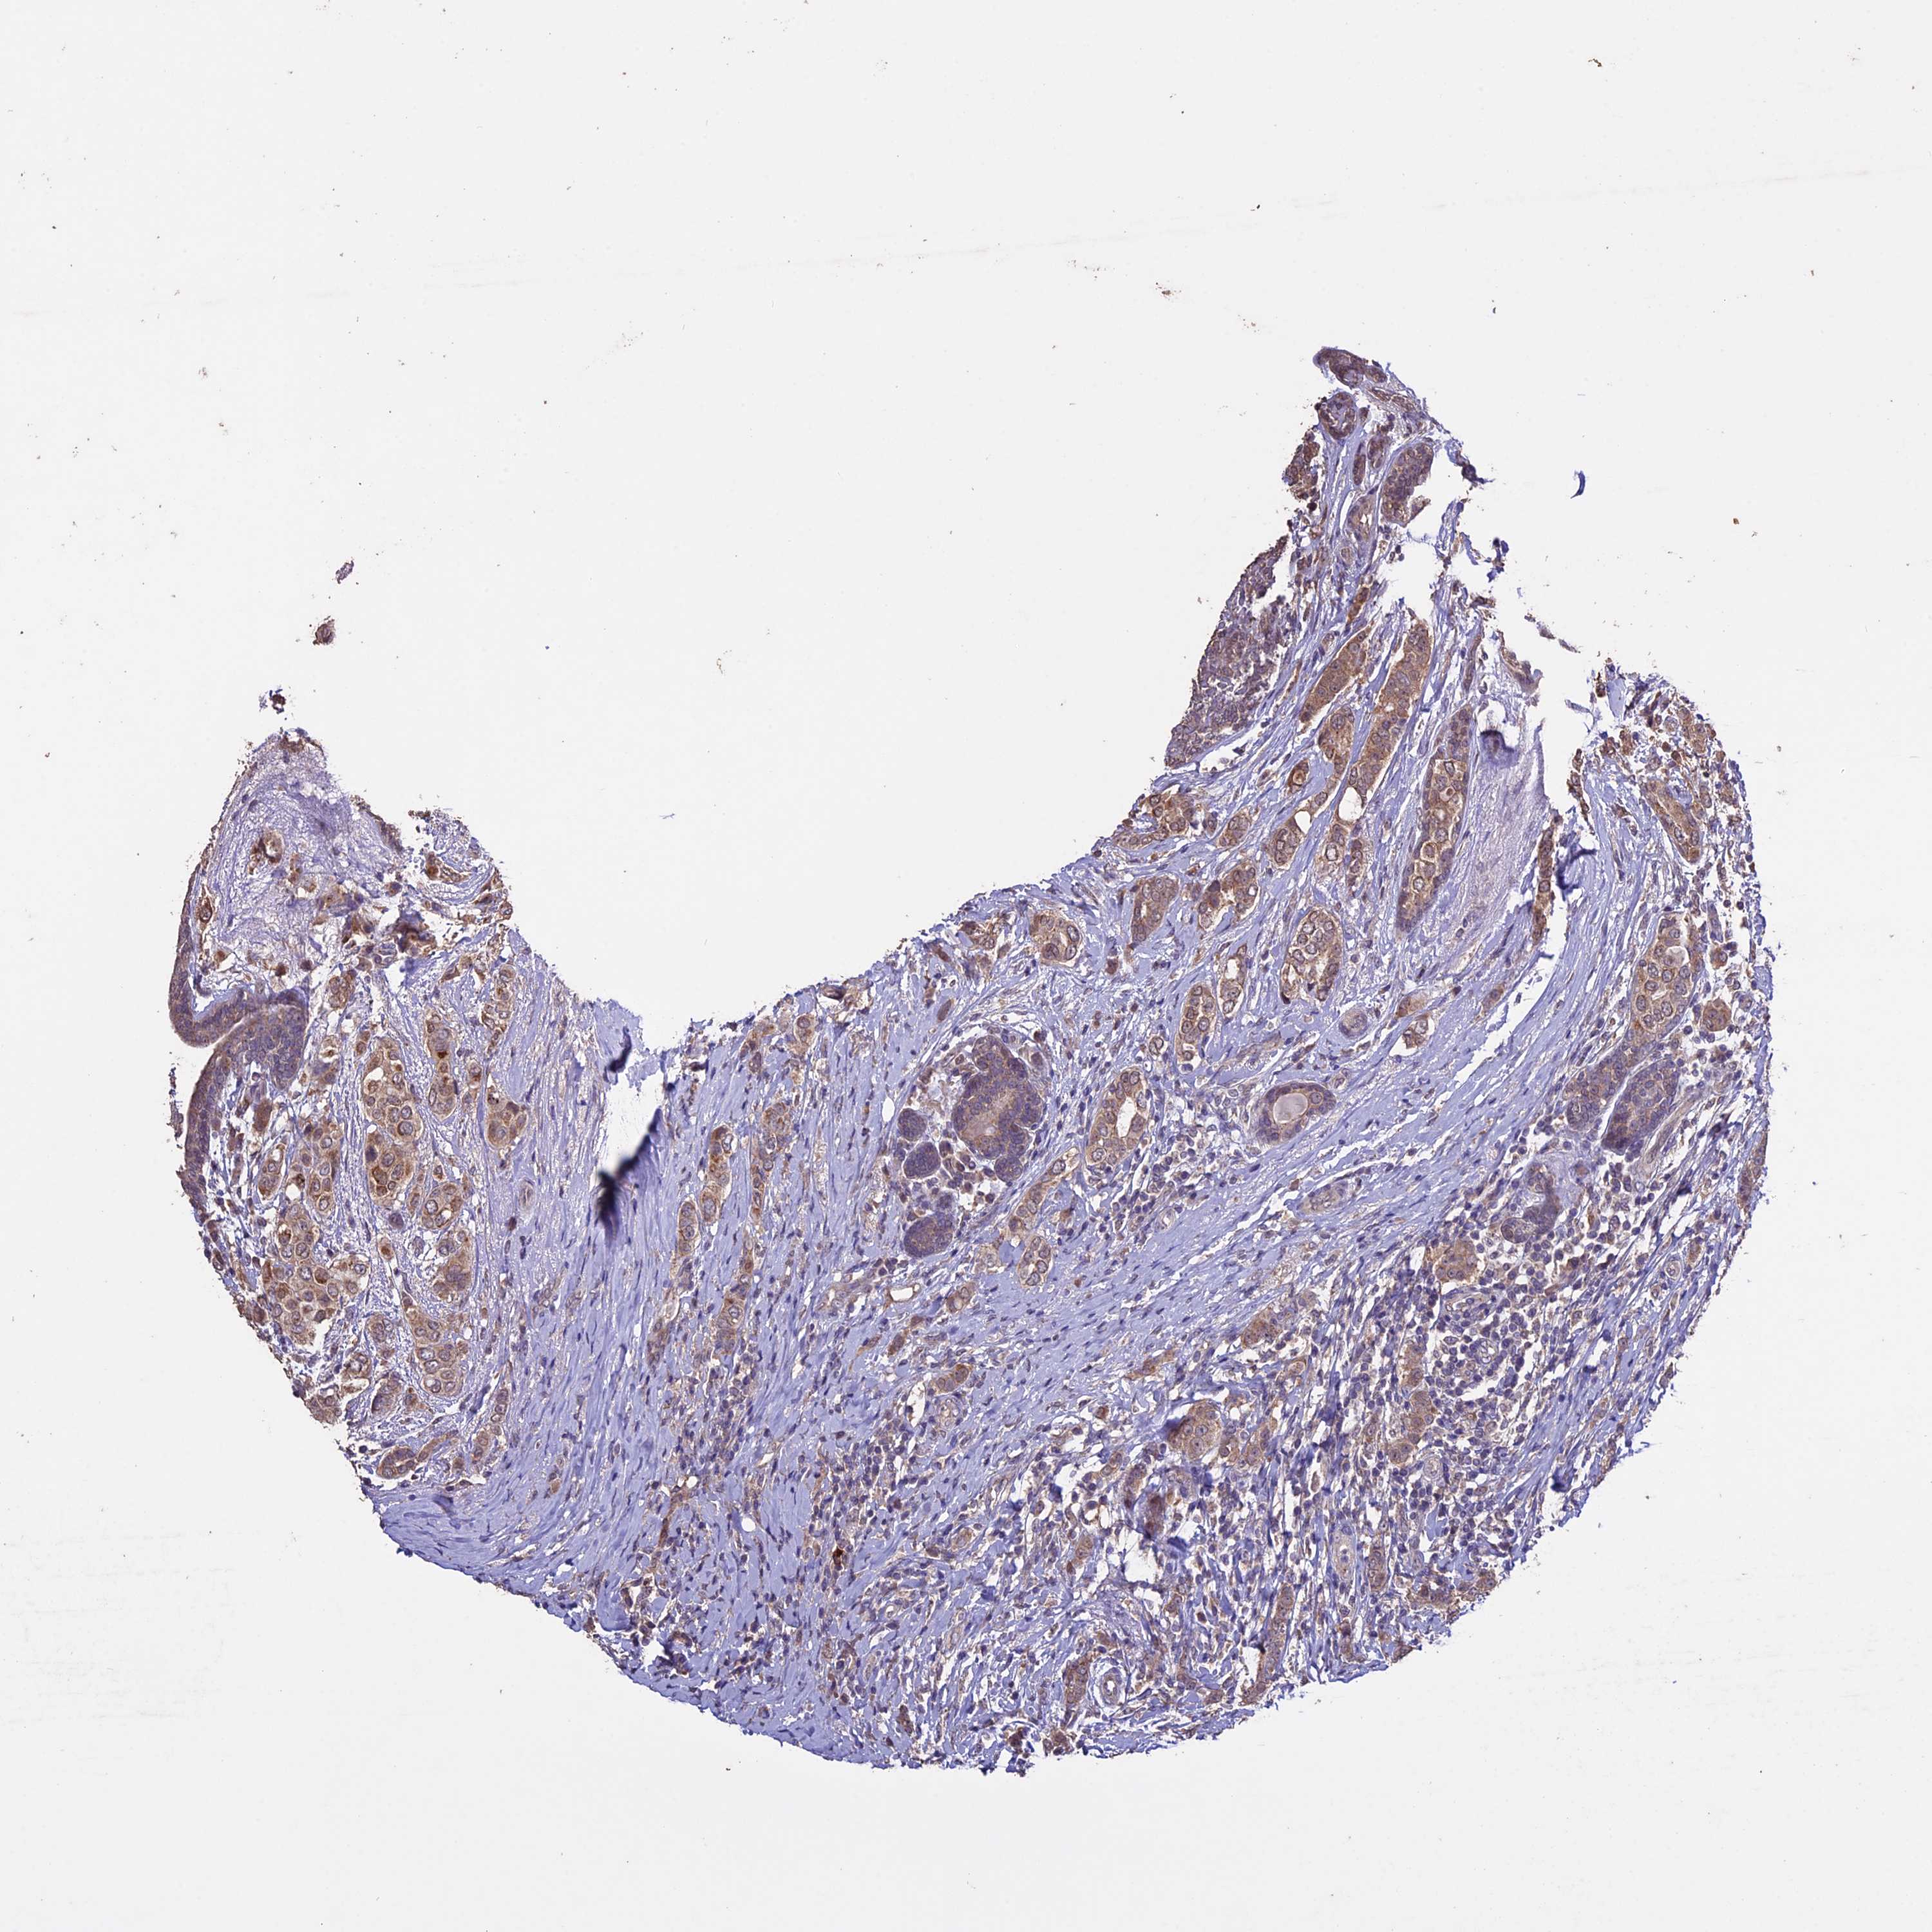

CANCER BREAST CANCER Show tissue menu

BRCA TCGA BRCA VALIDATION PROTEIN EXPRESSION